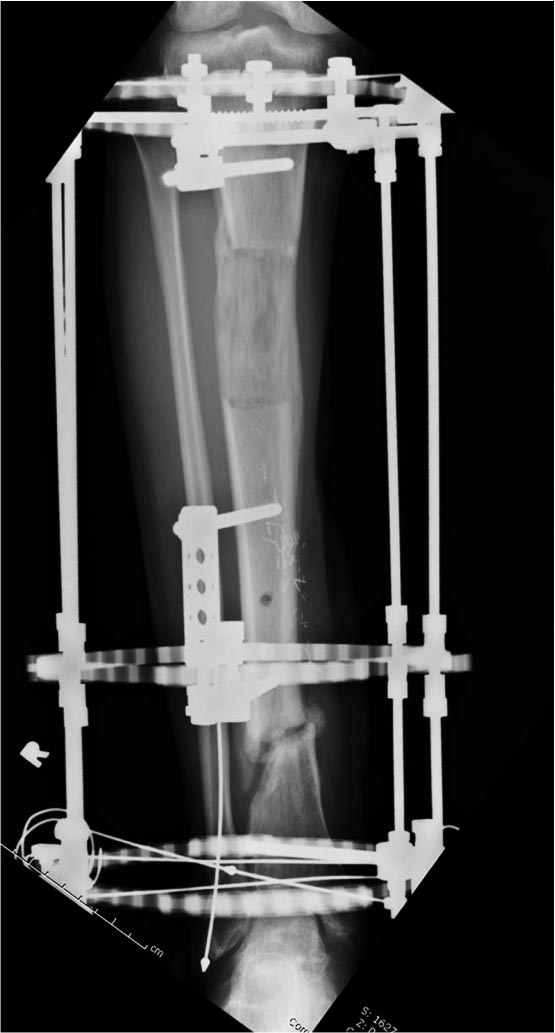

Данный случай не огнестрельная рана, а результат мотоциклетной аварии.

Независимо от повреждения при таких обширных дефектах мягких и костной

тканей применяется схожая тактика. Как видно, после нескольких I&D для

создания “pseudo membrane” применили цилиндрический блок из цемента.

Дефект мягких тканей закрыли свободным Anterior Thigh Graft. Из малого

доступа цилиндр удален небольшими кусочками, а пространство заполнили

бусами для освобождения пространства. По мере приближения регенерата

освободили пространство удалением бус через небольшой разрез. Этап

созревание регенерата можно было ускорить усилением интрамедуллярным

гвоздем, но решили закончить методом Илизарова.